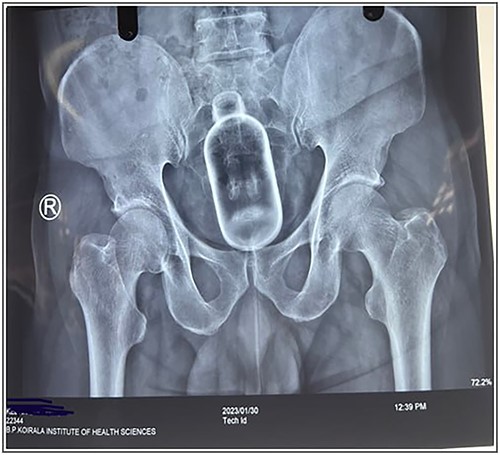

The rectal foreign body is a rare presentation at the Emergency Department. Whatever may be the motive whether it’s sexual gratification, concealment, body packers, sexual assault and, rarely, accidental the mortality and morbidity is high in the rectal foreign body as they only present for medical attention after several unsuccessful attempts to remove the object alone due to embarrassment. The standard technique for the trans-anal approach involves the combined use of analgesia, sedation, anesthesia and an attempt at manual removal of the foreign body. We hereby present a case of a male who was referred to the Emergency Department with a cough syrup bottle in his rectum. A 58-year female was admitted in emergency with a foreign body stuck in the anal canal for 24 h. He is a known case of psychiatric illness not under medication. It was acute in onset that happened while he was scratching his anal area with a cough syrup bottle. Following insertion, he developed severe pain and was unable to pass stool flatus; however, there was no per rectal bleed. He gives no history of past medical or psychiatric illness. His vitals were within normal limits and systemic examination was within normal limits. At emergency X-ray of the abdomen and pelvis was done, which showed a foreign body in the anal canal (Figs 1 and 2). Blood investigations were within normal limits. Digital rectal examination was done; however, no mass or foreign body was palpable. The patient underwent emergency manual removal of the foreign body via obstetric forceps under general anesthesia. Operative findings showed a foreign body (cough syrup bottle) of size 10 cm × 15 cm in the distal rectum about 8 cm above the anal verge (Fig. 3). The patient developed severe pain and stool incontinence and so was admitted at the ward and kept under observation. Psychiatric and cermatology consultation was done and the patient was discharged on the second postoperative day under oral medication. Sigmoidoscopy was done on a follow-up, which showed normal findings with minimal mucosal tear without perforation.

X-ray showing abdomen and pelvis with foreign body with no signs of perforation.